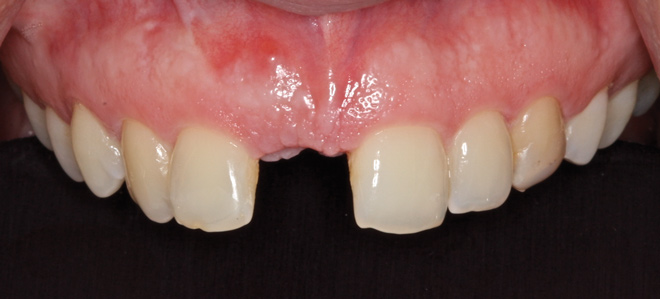

The patient was brought back weekly for 4 weeks for postoperative follow-up. Healing was satisfactory (Figure 18). Four months after implant placement, the final restoration, a porcelain-fused-to-metal screw-retained crown, was inserted at site No. 8 (Figure 19).

Fig 18. Healing at 3 months.

Figure 18